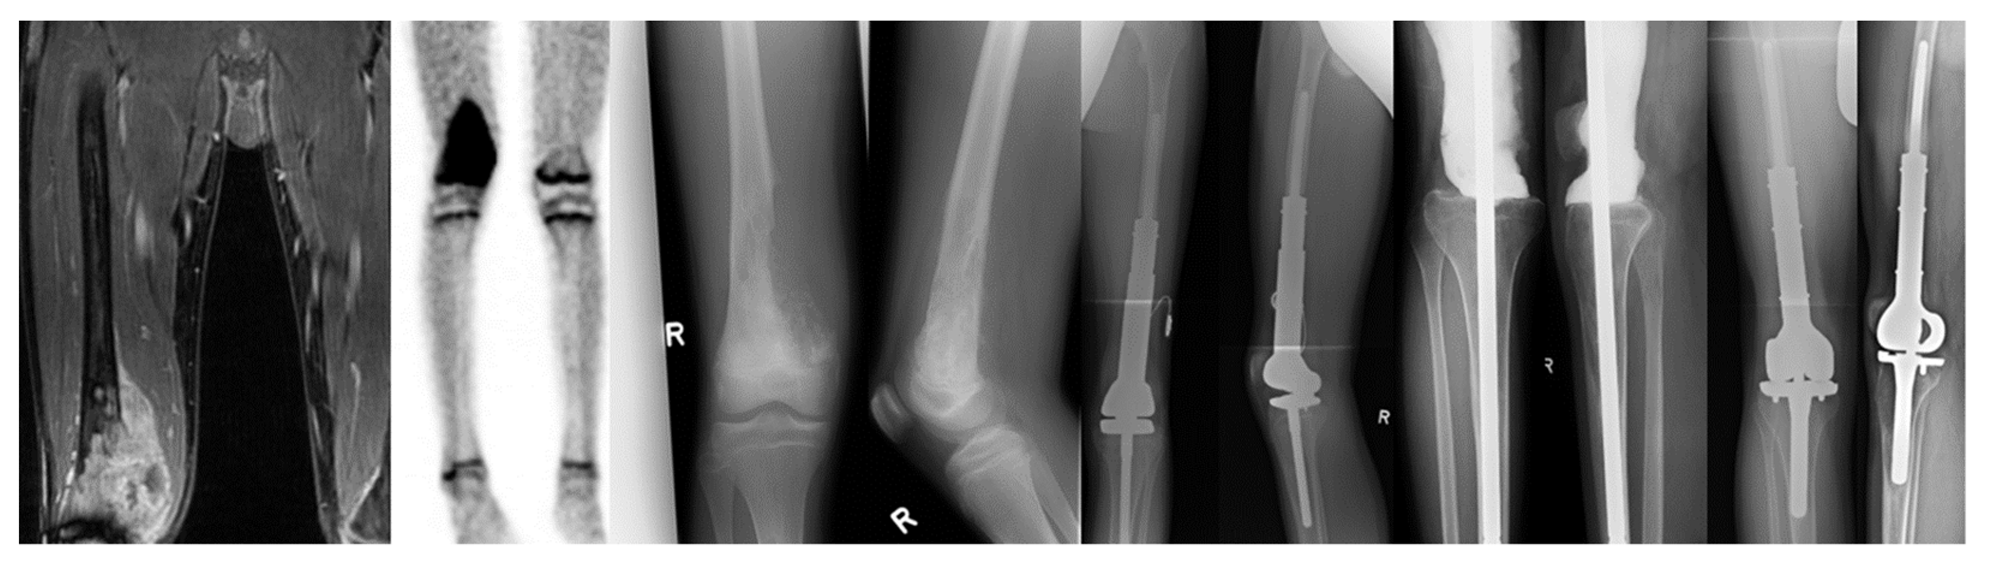

| Male | 63 | 2 | Chondrosarcoma, proximal tibia | 4.6 months | Streptococcus agalacticae, Enterococcus faecalis | 226 mg/L | 10.5 /nL | Indifferent | Unacid | 3x debridement; then DAIR | 7.0 years | No re-infection; tumor survivor |

| Female | 22 | 3 | Osteosarcoma, distal femur | 1.4 months | Staphylococcus aureus, Enterococcus faecalis | 87.6 mg/L | 5.9 /nL | Infection | Unacid, Ciprofloxacin, Rifampicin | 2x debridement; then DAIR | 7.0 years | No re-infection; tumor survivor |

| Male | 25 | 2 | Osteosarcoma, distal femur | 95.9 months | Negative (fistula) | 21.2 mg/L | 7.8 /nL | n.a. | Unacid, Vancomycin | Debridement | 5.9 years | Re-infection after 67 days (Staph. epidermidis; DAIR); then, infection freedom; tumor survivor |

| Male | 65 | 2 | Chondrosarcoma, proximal tibia | 243.8 months | Streptococcus dysgalactiae | 232.9 mg/L | 14.4 /nL | Infection | Ampicillin/Sulbactam | DAIR | 3.7 years | Re-infection after 21 days (Staph. Epidermidis; three-stage exchange) and after 664 days (Streptococcus agalacticae; DAIR); then, infection freedom; tumor survivor |

| Male | 22 | 2 | Osteosarcoma, distal femur | 0.6 months | Negative (wound healing delay; purulence) | 6 mg/L | 4.3 /nL | n.a. | Unacid | Debridement and drain | 1.3 years | No re-infection; tumor survivor |

| Female | 85 | 2 | Chondrosarcoma, distal femur | 24.8 months | Enterococcus faecalis | 28.2 mg/L | 9.1 /nL | Infection | Unacid, Vancomycin | Debridement; then removal and permanent arthrodesis | 2.1 years | No re-infection; tumor survivor |

| Male | 53 | 1 | Synovial-sarcoma, proximal tibia | 148.8 months | Staphylococcus capitis, Corynebacterium sp. | 27.3 mg/L | 10.9 /nL | Infection | Cotrimoxazole, Tazobactam, Vancomycin, Ciprofloxacin, Daptomycin, Levofloxacin, Rifampicin | Three-stage exchange | 6.6 years | Amputation for infection persistence after 414 days (Staphylococcus aureus, Staph. epidermidis); tumor survivor |

| Female | 49 | 3 | Ewing sarcoma, distal femur | 250.6 months | No reports available (external surgery) | 2.4 years | No re-infection; tumor survivor | |||||

| Female | 14 | 2 | Ewing sarcoma, distal femur, proximal tibia | 22.9 months | Streptococcus agalacticae | 12.5 mg/L | 6.6 /nL | Infection/Indifferent | Unacid, Vancomycin | DAIR | 5.4 years | Re-infection after 95 days (culture negative, two-stage exchange with tibial component retention); then, infection freedom; tumor survivor |

| Total femur arthroplasty (tumor of the entire femur; removal of entire femur; femoral head, femur shaft, and total knee arthroplasty) | ||||||||||||

| Male | 15 | 2 | Myxofibrosarcoma, entire femur | 0.9 months | E. coli, Staph. epidermidis | 268.0 mg/L | 5.8 /nL | Infection | Unacid, Ciprofloxacin | One-stage exchange | 1.3 years | No re-infection; death by tumor |

| Hip (total hip arthroplasty was performed in both cases) | ||||||||||||

| Female | 64 | 2 | Chondrosarcoma, proximal femur | 37.7 months | Staph. epidermidis | 6.2 mg/L | 8.8 /nL | Infection | Cotrimoxazole, Rifampicin | One-stage exchange | 6.2 years | No re-infection; tumor survivor |

| Male | 81 | 3 | Chondrosarcoma, proximal femur | 13.9 months | Staph. epidermidis, Candida albicans | 99.1 mg/L | 10.4 /nL | No information concerning infection | Cotrimoxazole, Voriconazole, Clindamycin | DAIR, then 2x debridement | 0.8 years | No re-infection; tumor recurrence with hemipelvectomy after 57 days; non-tumor associated death |

| Shoulder (total shoulder arthroplasty was performed in both cases) | ||||||||||||

| Female | 44 | 2 | Chondrosarcoma, proximal humerus | 5.1 months | Streptococcus sanguinis | 20.5 mg/L | 9.6 /nL | No infection | Unacid | Debridement | 5.1 years | No re-infection; death by tumor |

| Male | 68 | 3 | Renal cell carcinoma metastasis, proximal humerus | 1.4 months | Klebsiella oxytoca | 74.6 mg/L | 9.9 /nL | Infection | Ciprofloxacin, Unacid | 2x Debridement | 2.2 years | No re-infection; death by tumor |